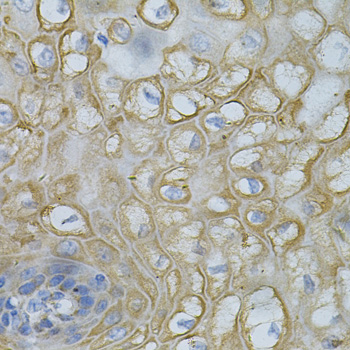

Immunohistochemistry of paraffin-embedded human colon using DEFB132 at dilution of 1:100 (40x lens).

,

Immunohistochemistry of paraffin-embedded human esophagus using DEFB132 at dilution of 1:100 (40x lens).

Immunohistochemistry of paraffin-embedded mouse kidney using DEFB132 at dilution of 1:100 (40x lens).